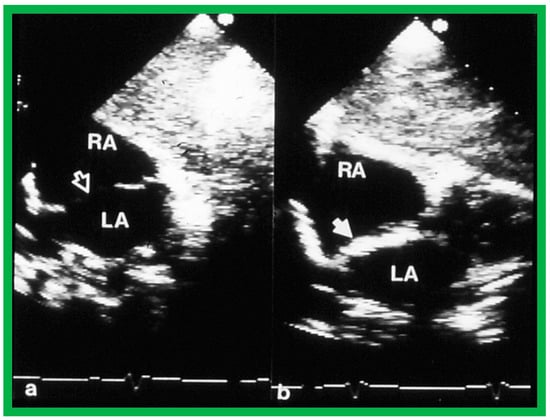

2. Diagnosis

9. Follow-Up after Device Occlusion

9.2. Device Position

9.8. Device Migration